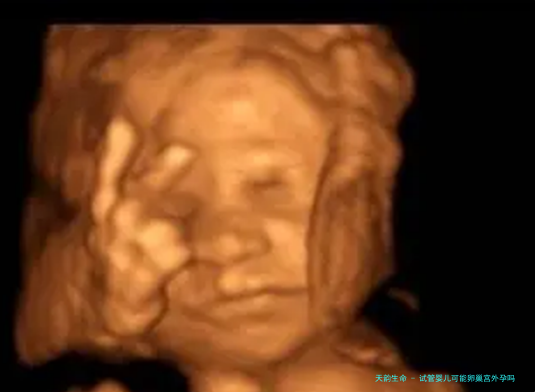

试管婴儿可能卵巢异位妊娠吗?谜底是肯定的。试管婴儿技术自己及厥后续过程中可能诱发的炎症反映等可能导致卵巢异位妊娠发生的可能性。

试管婴儿的技术是在体外进行受精,并将受精卵移植到子宫内施行妊娠的一种生殖技术,所以受精的可能性大大高于其他方法。妊娠的可能性在试管婴儿的治疗期间相比对较高,而宫外孕的概率则相对较低。